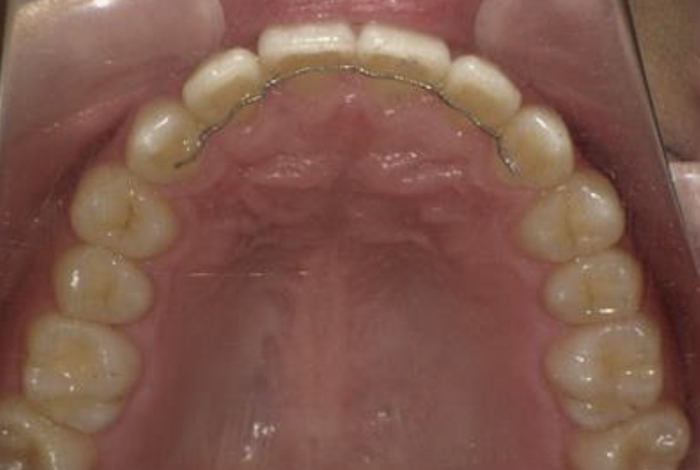

| 矯正装置装着時 | |

![]() |

| 年齢/性別 | 30歳/男性 |

| 治療内容 | 上の前歯のでこぼこが気になるとのことで来院しました。部分的なご希望のみでしたので、通常の表側装置を使用して治療を行いました。 |

| 治療期間 | 装置装着期間は、5か月です。その後安定させるための保定装置を1年ほど使用して頂きました。 |

| 治療上でのリスク | 歯の移動により歯根が吸収され短くなる可能性があります。歯の動き具合には個人差があります。衛生面が不良となりコンディションを損ねる可能性があります。 |

| 治療費 (全て税抜き) |

検査・診断 ¥25,000 |

| 装置代 ¥150,000 | |

| 毎月1度の調節料 ¥5,000 | |

| 保定観察料 ¥5,000 |